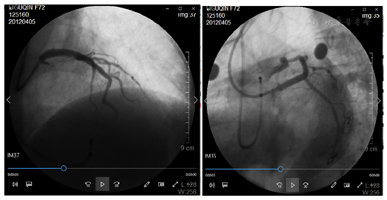

考虑回旋支开口处出现壁内血肿可能性大。其后使用第2条Runthough NS导引导丝进入回旋支远段血管,2.0 mm×15.0 mm顺应性球囊(sprinter)10个大气压先后扩张回旋支中段狭窄处和回旋支开口支架网眼处。其后自回旋支中段至开口狭窄处由远及近先后精确定位植入2枚火鸟2.5 mm×18.0 mm药物洗脱支架,两支架重叠约3 mm。其后于左主干及前降支近段支架内使用4.0 mm×12.0 mm非顺应性球囊(sprinter)18个大气压扩张。造影复查,左主干、前降支及回旋支支架内未见明显残余狭窄,前向血流TIMI 3级(图3)。手术期间患者每3~5分钟出现1次三度房室传导阻滞并心室停搏,每次均进行心脏按压、静推阿托品后恢复窦性心律,至冠脉介入治疗结束时共发生6次。其后植入临时起搏器,起搏频率60次/min(图4)。

临时起搏器植入后观察20 min,患者起搏心律和窦性心律交替出现,血压稳定(120/65 mmHg左右),返回病房。急查电解质正常,肌钙蛋白T 0.5 ng/ml。术后12 h内患者反复恶心、呕吐,不能进食,术后第2天出现血压下降(80/45 mmHg左右),但神志清醒,两肺呼吸音粗糙,无啰音,四肢温度偏低,尿量减少(30~50 ml/h)。急查床旁超声未见心包积液,N端利钠肽前体3960 pg/ml。考虑心力衰竭合并低血压状态。立即快速补液(3000~5000 ml/d),并持续泵入多巴胺,最大剂量为15 μg/(kg·min),血压维持在100~130/60~80 mmHg,随后多巴胺及液体逐渐减量。患者术后第3天完全恢复窦性心律,心电图较术前无明显变化,拔除临时起搏电极。术后第8天复查肌钙蛋白T 0.06 ng/ml,N端利钠肽前体880 pg/ml。心脏超声示左室舒张末期前后径42 mm,射血分数56%。停用多巴胺。术后第14天患者连续步行2 km,无胸痛、心慌发作。其后出院。